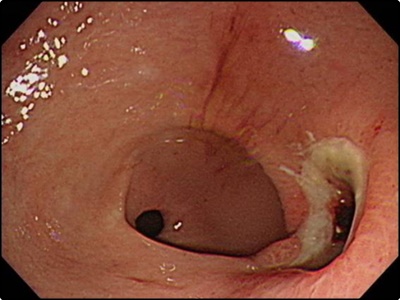

위암 초기증상: 무증상

조기 위암 환자의 경우 약 80% 가량은 위암 초기증상등의 증상을 느끼지 못했다고 합니다. 아무런 전조증상이 없다가 갑자기 위염인가 싶을 정도의 가벼운 속 쓰림 증세가 나타나게 됩니다. 이렇게 되면 이미 조기진단과 자가진단의 시기를 놓쳐 암을 키우는 경우가 많다고 합니다. 그러니 예방차원에서 정기적인 정기검진은 꼭 필요합니다.